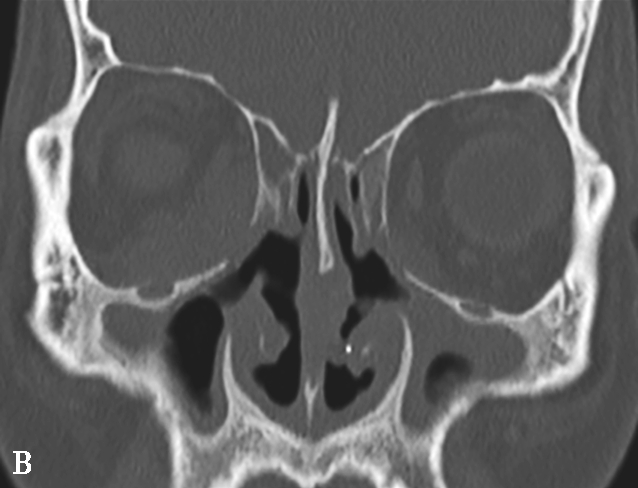

图1-3-26 鼻腔鼻窦肉芽肿性多血管炎

A、B.横断面CT及冠状面CT骨窗,示鼻背部塌陷,鼻中隔、双侧筛窦及上颌窦黏膜增厚,窦壁骨质增生硬化,内缘骨皮质欠光整;双侧中、下鼻甲形态欠自然,双侧眼眶内下壁骨皮质部分缺损,邻近内下象限肌锥外间隙可见弥漫性软组织增厚影,右侧为著;双侧上颌窦口-鼻道复合体增宽,钩突缺如;C.横断面T 1 WI,示双侧上颌窦腔可见略低信号,气-液平面可见,鼻背部塌陷,鼻中隔黏膜增厚,鼻咽顶后壁软组织增厚,呈等信号;D.横断面T 2 WI,示上颌窦腔病变呈高信号,余病变呈略低信号;E.横断面T 1 WI+FS+C,示窦腔、鼻中隔增厚,黏膜及其他受累结构呈中等强化,双侧翼腭窝及上颌窦后脂肪间隙受累,强化;F.冠状面T 1 WI+FS+C,示双侧眼眶内下象限肌锥外间隙病变呈中等强化,大脑纵裂及额部脑膜受累,呈弥漫性增厚强化

4.CT表现

①平扫表现:首先侵犯鼻部中线区,鼻中隔和双侧中下鼻甲及上颌窦内壁骨质破坏,伴有不规则索条影;双侧上颌窦腔缩小,黏膜增厚,窦壁骨质硬化、肥厚,可出现“双线”征;最终导致上颌窦内壁、筛窦间隔、纸样板、筛板、鼻甲和鼻中隔明显破坏而形成大空腔,类似术后改变。鼻窦周围软组织浸润,眼眶是该病窦外侵犯的首发部位,很少累及颅底、翼腭窝、窦后区和鼻咽部(图1-3-26A、B)。②增强扫描表现:鼻腔及鼻窦可见结节状及肿块样黏膜增厚强化。

5.MRI表现

①T 1 WI表现:呈低至中等信号的结节状肿块影。②T 2 WI表现:早期T 2 WI多为高信号,中晚期多为结节状肿块影(与高信号的水肿黏膜相比),提示为纤维组织,当病变呈急性加重并侵犯邻近的软组织时,表现为软组织水肿高信号。③增强扫描表现:病变区黏膜呈结节状或肿块状强化,周围受累组织呈明显不均匀强化(图1-3-26C~F),TIC(时间-信号强度曲线)整体呈平缓型,早期缓升,说明GPA与TIC单纯表现为平缓型的普通良性病变相比血管通透性更高或血管数量更为丰富,致使对比剂早期更易透过血管进入血液,产生更高的流速造成早期时相内曲线斜率略升高,这与该病的多血管炎症的发病机制密切相关。